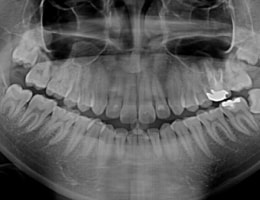

当院のデジタルレントゲンは、

従来のフィルムを使用したレントゲン撮影に比べ、

人体に受ける放射線の量を、約1/4~1/10に抑える事が可能です。

照射時間がかなり短く、安心安全です。

大きなパノラマレントゲンは歯並びなど、全体像をつかむことにも有効的ですが、

現状を詳細に把握するため、小さいレントゲンを10枚撮って診断・治療をしております。

これにより歯石、歯周ポケット等も詳細に把握でき、緻密な治療を提供することが出来ます。